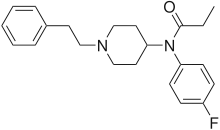

Anilidopiperidines

- 3-Allylfentanyl

- 3-Methylfentanyl

- 3-Methylthiofentanyl

- 4-Phenylfentanyl

- Alfentanil

- α-Methylacetylfentanyl

- α-Methylfentanyl

- α-Methylthiofentanyl

- Benzylfentanyl

- β-hydroxyfentanyl

- β-hydroxythiofentanyl

- β-Methylfentanyl

- Brifentanil

- Butyrfentanyl

- Carfentanil

- Fentanyl

- Lofentanil

- N-Methylcarfentanil

- Mirfentanil

- Ocfentanil

- Ohmefentanyl

- Parafluorofentanyl

- Phenaridine

- R-30490

- Remifentanil

- Sufentanil

- Thenylfentanyl

- Thiofentanyl

- Trefentanil

Structures